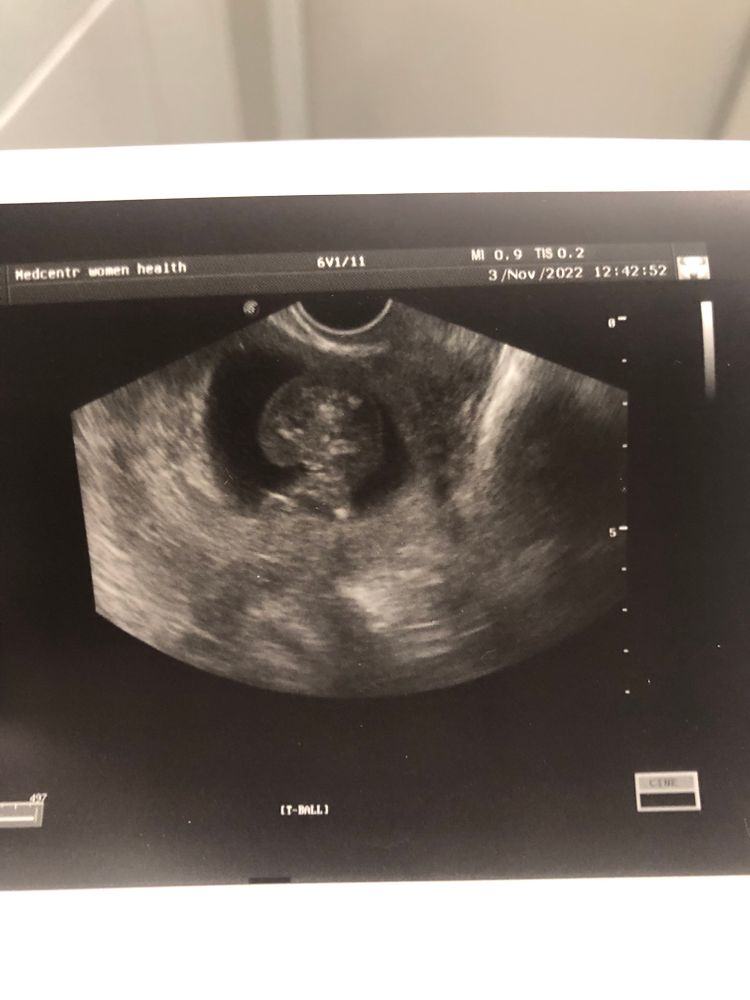

Tereza Am, но справедливости ради ракурсы с пипиркой есть 🤣 даже два, третье узи разобрать уже не смогла 🤣

Блин еле разобралась шо где 🤣 не ясно пока. Вроде и правда торчит что то, но хз уж 😅